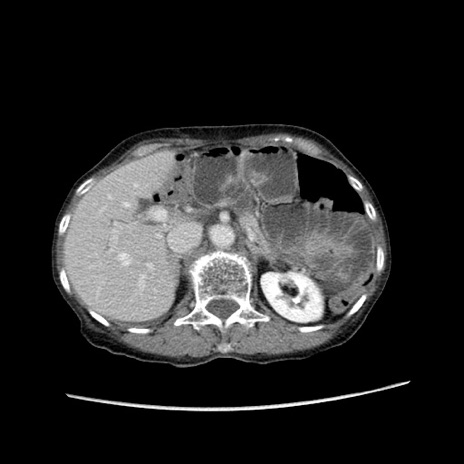

症例25(横断像)

【症例】80歳代女性

【主訴】胸のつかえ感

【現病歴】約9時間前に食後から胸のつかえた感じあり、嘔吐あり、来院。

【既往歴】胃癌(全摘)、胆摘、虫垂炎

【身体所見】心窩部に圧痛あり、反跳痛なし。

【データ】WBC 5700、CRP 0.05